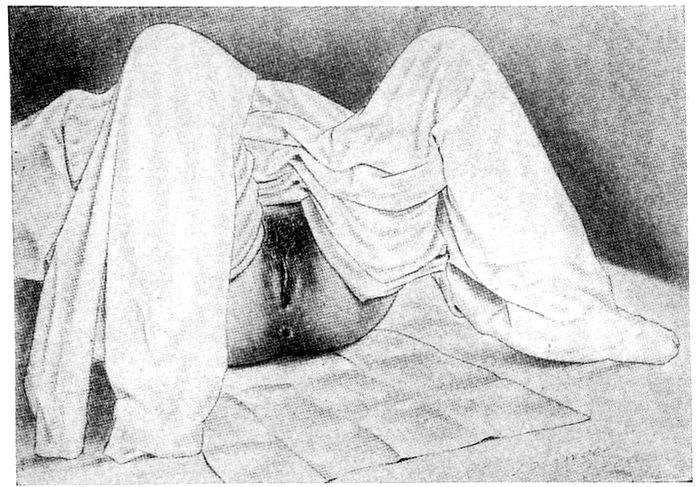

| 56. |

Patient draped for internal examination |

137 |